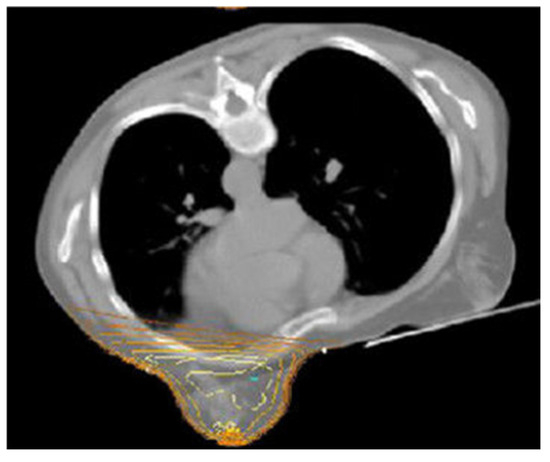

The Prone-Position Whole Breast Irradiation Paradox: Where Do We Stand? A Comprehensive Review

by Chris Monten, Ilaria Benevento, Antonietta Montagna, Edy Ippolito, Paola Anselmo, Luciana Rago, Barbara D’Andrea, Angela Solazzo, Antonella Bianculli, Raffaele Tucciariello, Giammaria Fiorentini, Vito Metallo, Simone Salvago, Carmen Santoro, Anna Vallario and Grazia Lazzari

Over the past two decades, interest in prone-position whole breast irradiation (WBI) as an effective and practical alternative to supine treatment has been growing a lot. Although solid scientific data has provided evidence of substantial dosimetric benefit with decreased toxicity, there is still [...] Read more.

Over the past two decades, interest in prone-position whole breast irradiation (WBI) as an effective and practical alternative to supine treatment has been growing a lot. Although solid scientific data has provided evidence of substantial dosimetric benefit with decreased toxicity, there is still conflict in the radiotherapy community over whether to adopt prone-position WBI as a valid alternative to supine radiotherapy (RT) in routine clinical practice. A large number of prone trials have been conducted to assess and address concerns related to prone treatment in large and pendulous breasts and in left and right breast cancer (BC), nodal irradiation, and its reproducibility with deep inspiration breath hold (DIBH) delivery with photons or protons. Appropriate atlases have been defined to improve prone nodal irradiation. Additionally, more comfortable customized immobilization couches have been constructed to permit IMRT beams and VMAT arrangements with modern LINACs. Although our search in literature databases shows a growing body of evidence from the past two decades on this issue, prone WBI is still underused. Given the paradox of the advances and benefits of this positioning and the lack of drive in the radiotherapy community towards its clinical implementation, the purpose of this comprehensive review is to evaluate the true advantages of this position in real life and contextualize it in scenarios like large breasts, left-sided breast cancer, and nodal irradiation to encourage its implementation in clinical practice. Full article

Show Figures

Figure 1